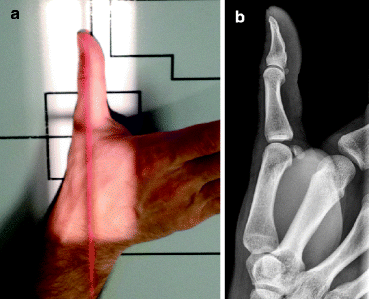

엄지측방향촬영 (thumb lateral projection)

google 이미지 참조

(2) 촬영방법

환자는 촬영대 끝에 앉도록 하고 팔꿈치를 약 90도 구부려 편안한 상태로 손을 상수용체(IR) 위에 올려 놓습니다.

손은 엎침(pronation)하여 손등을 약간 구부려 엄지를 옆으로 하고 손가락과 손을 활(arch)형태로 하고 손을 중간 정도 돌려 엄지가 바른 측면 자세가 되도록 합니다.

손을 쫙 피면 엄지는 사방향으로 되지만 손에 계란을 쥔듯 동그랗게 하면 측방향이 됩니다.

상수용체(IR) 장축과 엄지의 장축이 일치하도록 자세를 확인하고, 중앙에 첫째 손허리손가락관절이 오도록 합니다.

이때 엄지 전체가 포함되어 측면자세가 되도록 상수용체(IR)에 밀착시킵니다.

중심X선은 첫째 손허리손가락관절에 수직이 되도록 입사시킵니다.

X선관 초점-영상면 사이 거리(SID)는 최소한 100cm가 되도록 합니다.

(3) 영상평가

-엄지 전체와 손목뼈, 큰마름뼈(trapezium)가 상수용체(IR) 중심에 위치하여 나타나야하며, 조사야 중심에서 첫째 손허리손가락관절이 나타나야 합니다.

-관절 사이는 분리되어 잘 나타나야 합니다.

-움직임이 없는 상태에서 가장 적당한 X선조사로 연조직과 첫째 손허리뼈와 손가락뼈의 뼈 미세구조(trabecular)가 잘 나타나야 합니다.

-좌우표시(R 또는 L)는 조사야 범위 안에서 겹치지 않게 나타나야 합니다.